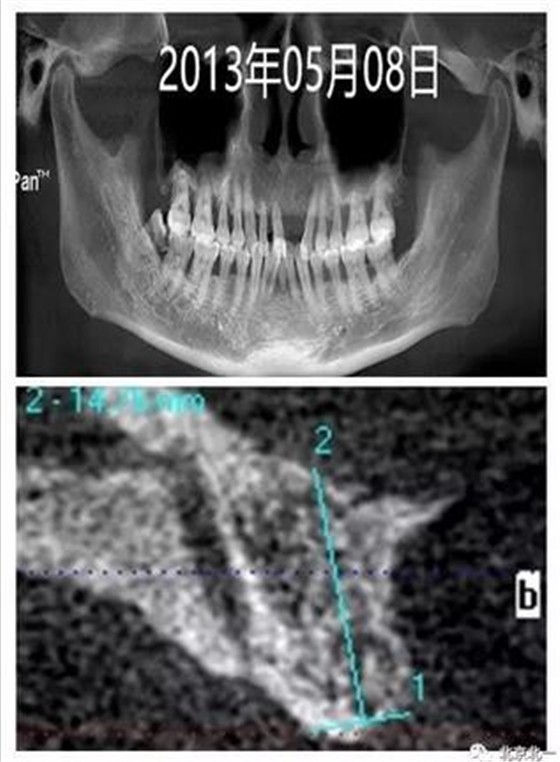

圖一:手術(shù)前CBCT

圖二:微創(chuàng)拔牙即刻種植當(dāng)天,采用ACTIVE 4.3*11.5,3.5*11.5(11 21位點(diǎn))